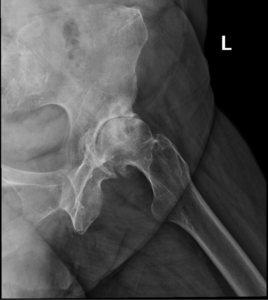

- Osteoarthritis: It is characterized by progressive wearing away of the cartilage of the joint. As the protective cartilage wears down, the bone ends rub against each other and cause pain in the hip. Rheumatoid arthritis: This is an autoimmune disease in which the tissue lining the joint (synovium) becomes inflamed, resulting in the production of excessive joint fluid (synovial fluid). This leads to loss of cartilage causing pain and stiffness.

- Traumatic arthritis: This is a type of arthritis resulting from a hip injury or fracture. Such injuries can damage the cartilage and cause hip pain and stiffness over a period of time.

Diagnosis

Diagnosis is made by evaluating medical history, physical examination and X-rays.